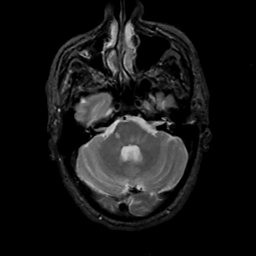

MR Study #12, May 12, 1991 -- Slice #12